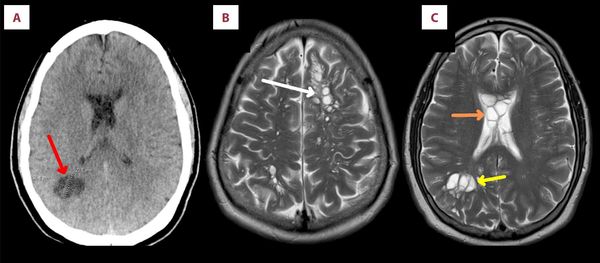

(迈阿密9日综合电)美国佛罗里达州一名男子因为严重偏头痛持续数月而求诊,医生透过电脑断层与核磁共振造影检查发现,男子的大脑中有绦虫(tapeworm)寄生,甚至在脑内产卵,刺激了头骨下组织,确诊为神经囊虫病(neurocysticercosis)。

综合纽约邮报等美媒报导,这起病例7日被刊登在《美国期刊病例报告》上,患者原本就有偏头痛、第2型糖尿病与肥胖病史,就诊前4个月偏头痛忽然加剧,原先服用的药物也不再见效。医生检查发现,他的大脑左右半球都有多个囊肿,伴随肿胀情形。

传染病专家证实,患者的大脑中有一种称为猪肉绦虫(又名有钩绦虫)的寄生虫存活,还在脑中产卵,头骨下的组织因此受到刺激。加上血检结果,确认他罹患神经囊虫病,并给予抗寄生虫、消炎药物治疗,2周后病情有所好转。